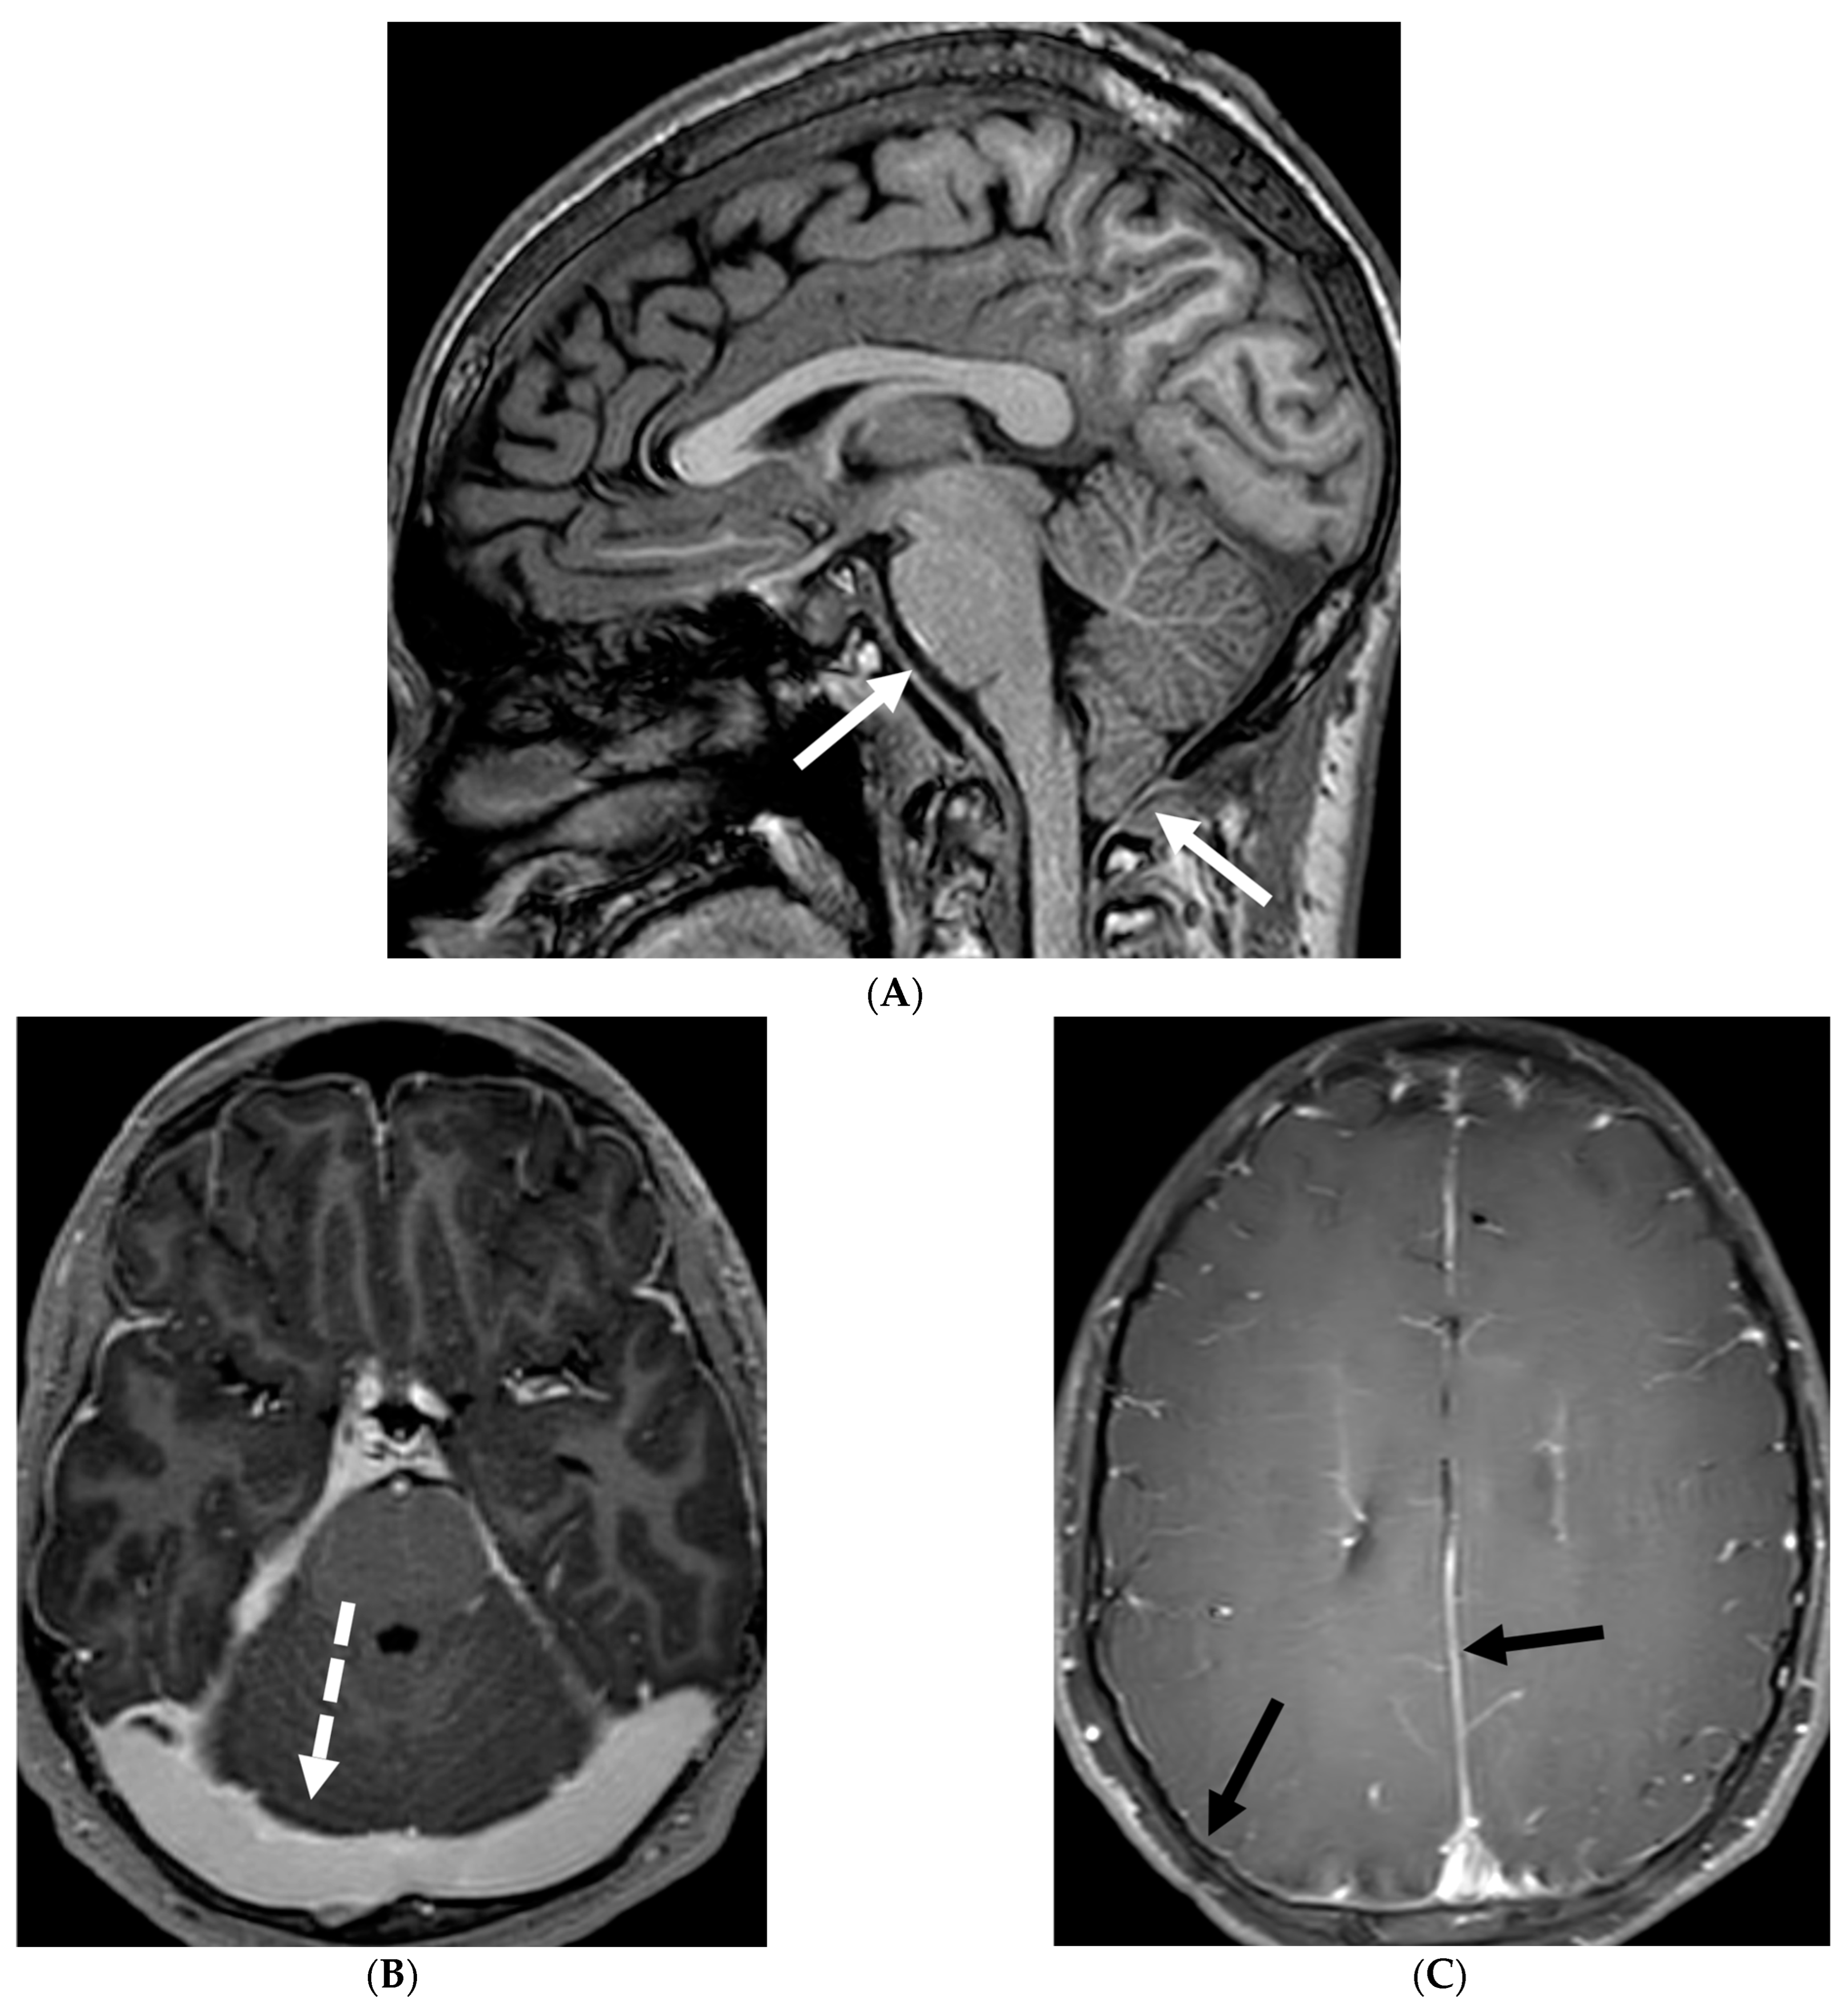

5.3. Anti-Myelin Oligodendrocyte Glycoprotein (MOG) Demyelination

Anti-MOG antibody associated demyelination (MOGAD) frequently presents as Acute Disseminated Encephalomyelitis (ADEM) in children and opticospinal involvement in young adults [105]. Bilateral but asymmetric T2 hyperintense lesions occur in thalamus, pons and cerebellar peduncles are common in children [106]. Optic nerve involvement typically presents as a long segment with anterior predominance, in contrast to the posterior predominance seen in Neuromyelitis Optica Spectrum Disorders (NMOSD) and the short segment involvement characteristic of Multiple Sclerosis (MS) [106].

LME has been shown to present early in the disease course and is much more common in children (33%) compared to adults (8%) [107]. Gadde et al. found that 8% of pediatric MOG antibody-associated demyelination cases had only LME without any other central nervous system manifestation. LME when present can be particularly helpful in differentiating from NMOSD [106]. Furthermore, Valencia-Sanchez et al. reported a significant association between LME and cerebral cortical encephalitis in MOG antibody-associated disease. This finding suggests that LME may be an important marker for cortical involvement and potentially more severe disease (Figure 21) [108].

Figure 21.

Sagittal T2 (A,B), axial FLAIR (C), axial T2 cervical spine (D) at the level of C7 vertebral body and Axial T2 orbits (E): 12-year-old girl presented with right focal motor seizure and left temporal lobe slowing on electroencephalogram (EEG). Right eye vision loss and irritability. Ill-defined areas of signal abnormalities are identified within the RIGHT mesial temporal lobe and bilateral medulla (white arrows). FLAIR hyperintensity is identified on the left central sulcus (black arrow). Small focus of signal abnormality is seen on the right side of the cord at the 7th cervical vertebra (C7) (dashed arrow). There is also bilateral papilledema (arrowheads). Post contrast axial T1 (F,G), axial T1 orbits (H) and axial T1 cervical spine at C7 (I): Asymmetric LME (black arrows) predominantly involving the left cerebral hemisphere, with minimal right parietal involvement is seen. Ill-defined enhancement in the right mesial temporal lobe, and right greater than left medulla (white arrows) corresponds to the signal abnormality. There is right greater than left, optic nerve enhancement (curved arrow). Single small enhancing lesion in the spinal cord on the right at the level of C7 corresponds to the signal abnormality (dashed arrow). Features favor a demyelinating process. MOG antibodies were positive at 1:20 in keeping with Myelin oligodendrocyte glycoprotein (MOG) antibody disease (MOGAD).